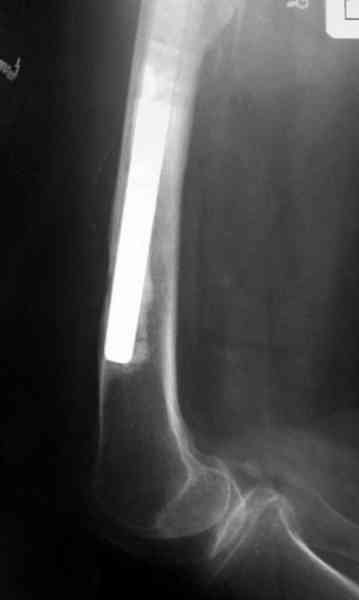

№3-6 снимки с осложнением

и последние снимки.